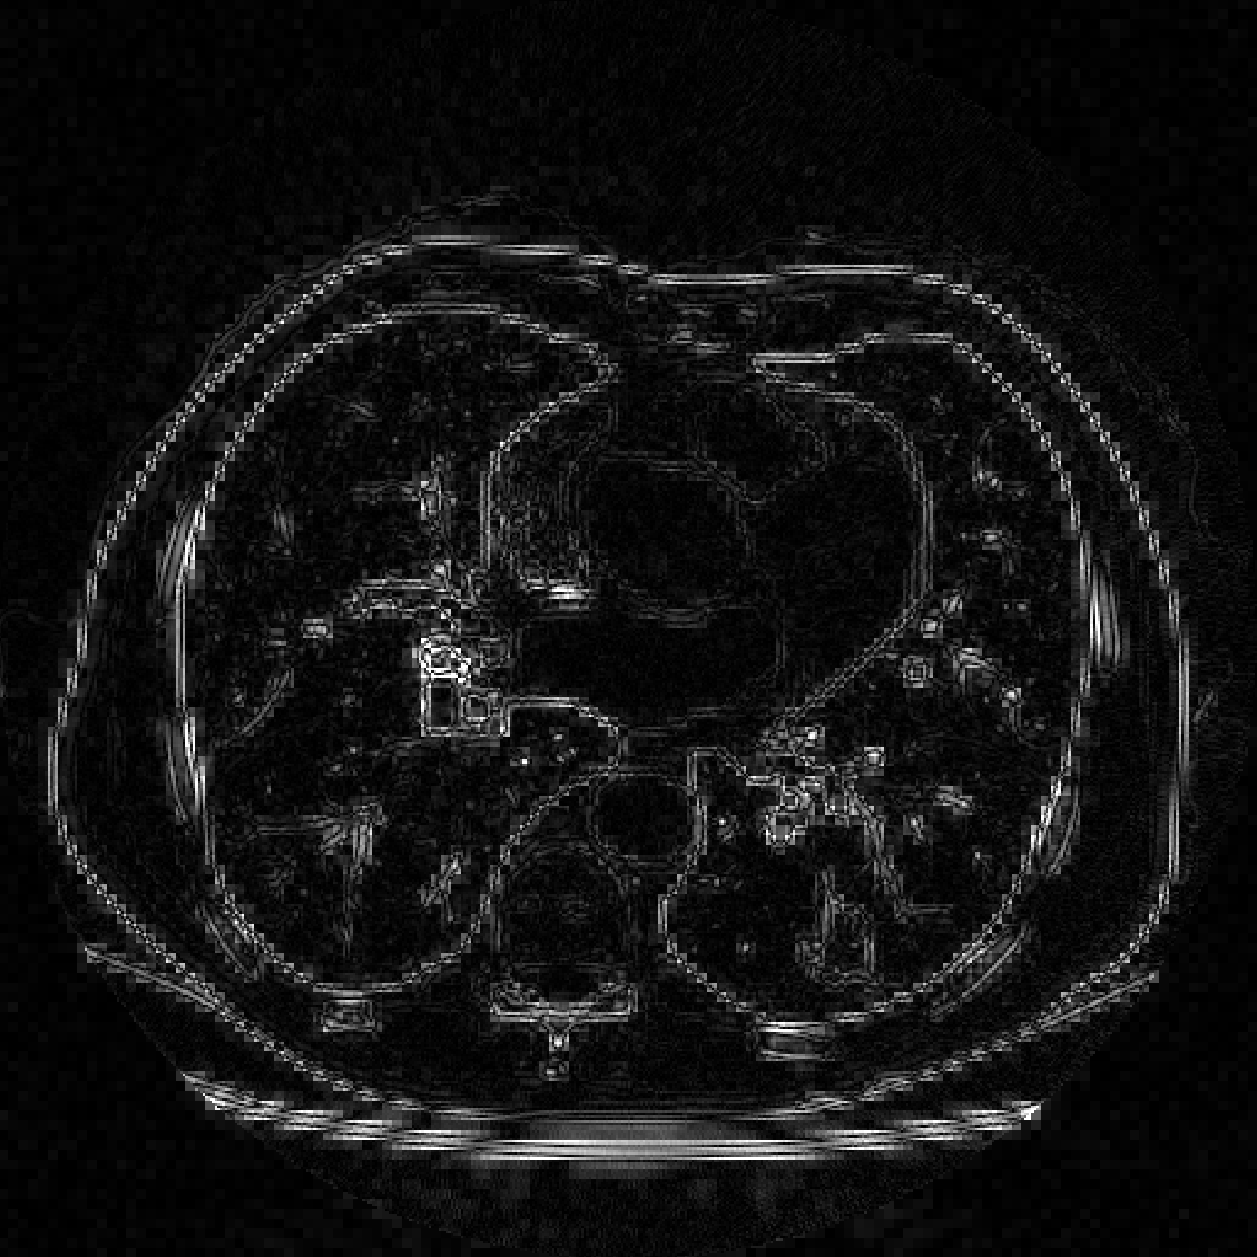

Fig.4 shows that our methods provide an improvement over the oblique method in our test cases. Fig.5 shows that our methods are more consistent when the resolution is relatively low. The reason is that oblique method truncates and estimates the sinc function, while we calculate the box spline exactly and have more accurate back projection. Fig.6 shows the absolute total error Etotalsubscript𝐸totalE_{\rm total} of the real CT image, the image reconstructed by oblique method suffers from higher error.

Refer to caption

(a)

(b)

(c)

Fig. 6: Absolute total error Etotalsubscript𝐸totalE_{\rm total} for the oblique method and box spline method on a real CT image. (b) and (c) are shown in the same scale to show the relative size of errors. (a) Ground truth. (b) Box spline, SNR = 16.7dB, SSIM = 0.84. (c) Oblique, SNR = 14.7dB, SSIM = 0.75.